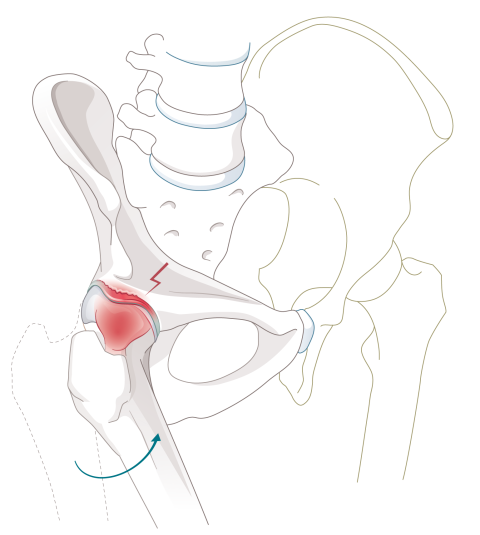

Das Hüftimpingement (auch femoroacetabuläres Impingement-Syndrom oder kurz FAIS) bezeichnet die ungünstige mechanische Form der Hüfte, die ein Anschlagen oder Anstehen des Kopfes und des Schenkelhalses gegen die Pfanne verursacht. Die Hüfte wirkt bei bestimmten Bewegungen und Positionen wie blockiert. Hierfür gibt es verschiedene Gründe: Einerseits kann der Hüftkopf (die Gelenkkugel) knöcherne Anlagerungen am Rand aufweisen, so dass er seine runde Form verliert (fehlende Taillierung bis hin zu einem Buckel). Diese Formstörung führt zu einem sogenannten Cam-Impingement. Andererseits kann auch die Gelenkpfanne (Acetabulum) zu tief oder ungünstig verdreht sein, so dass sie den Hüftkopf zu stark umfasst. Diese Formstörung führt zu einem sogenannten Pincer-Impingement.

Am häufigsten liegt eine Kombination aus beiden Varianten vor (sogenanntes Misch-Impingement). Die beschriebenen Formveränderungen führen dazu, dass der Übergang von Hüftkopf zu Schenkelhals an die Gelenkpfanne und das um die Pfanne herumlaufende Labrum (Gelenklippe) anschlägt. Je häufiger es zu einem solchen Anschlagen kommt und je höher die Geschwindigkeit und die Krafteinwirkung dabei sind (z. B. bei gewissen Sportarten), desto früher werden der Gelenkknorpel und/oder der Pfannenrand bzw. das Labrum beschädigt. Dabei entzündet sich das Gelenk und es kommt zu Schmerzen. Auf Dauer kann ein Hüftimpingement zu einer Arthrose führen

1: Hüftpfanne, die den Kopf zu stark umfasst (Pincer-Impingement) 2: Fehlende Taillierung / Buckel (Cam-Impingement) 3: Gelenklippe (Labrum)